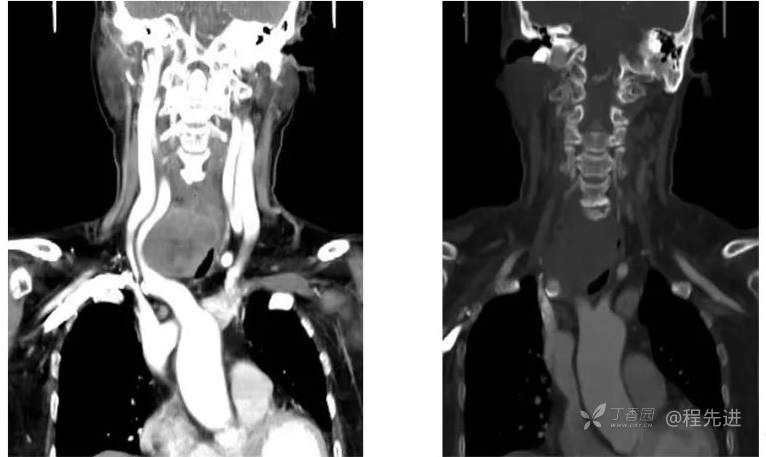

CT

冠状位重建

左增强,右骨窗